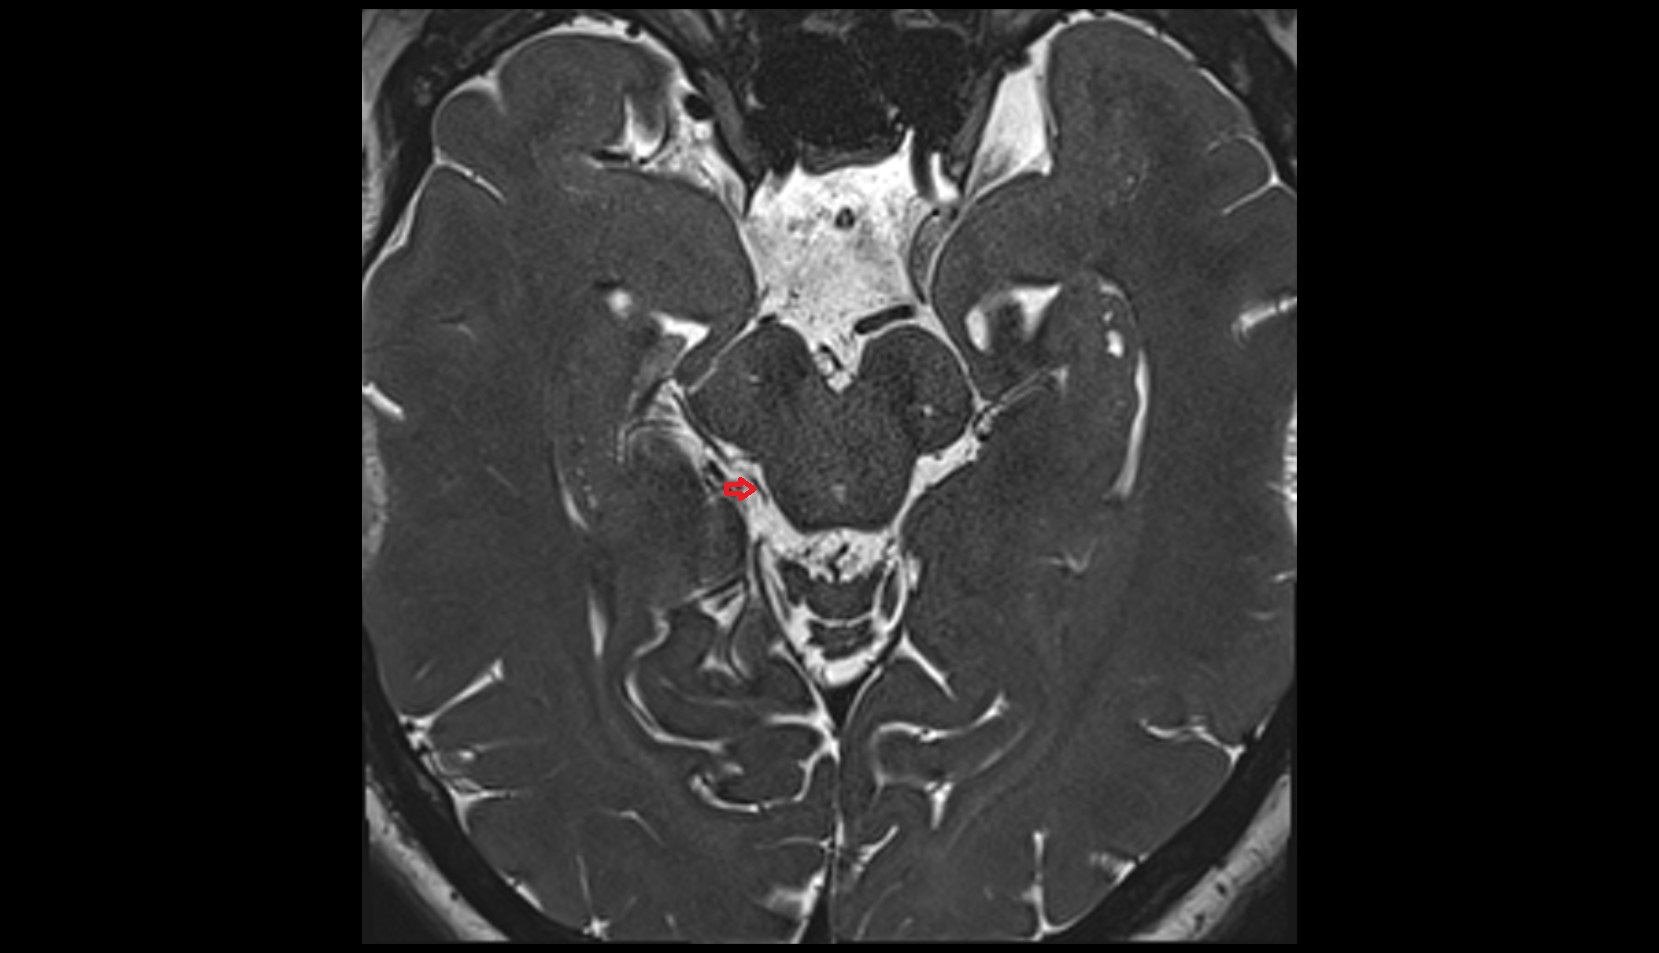

- Lateral aperture of fourth ventricle (foramen of Luschka)